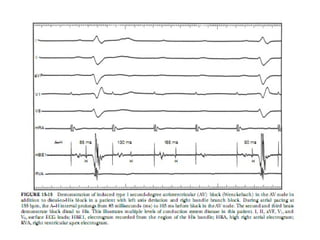

• Basic conduction intervals:

Prolongation of the H-V interval > 70 msec

is an indication of infra His disease and in

symptomatic patient this may indicate

permanent pacing in patients with 1st

degree HB or BBB while A-H prolongation

is not as significant.

• In contrast to the AH interval, the HV interval

remains relatively constant during incremental atrial

pacing, and block below His (infra-Hisian or intra-

Hisian block) is considered pathologic at pacing

cycle lengths greater than 400 ms (rates <150

beats/min).

• In symptomatic patients:

Long HV intervals (≥70 to 100 ms) and

block below the His bundle at atrial pacing

rates of less than 150 beats/min (≥ 400

ms) indicate disease in the His-Purkinje

system and are associated with a

relatively high incidence of subsequent

complete heart block.